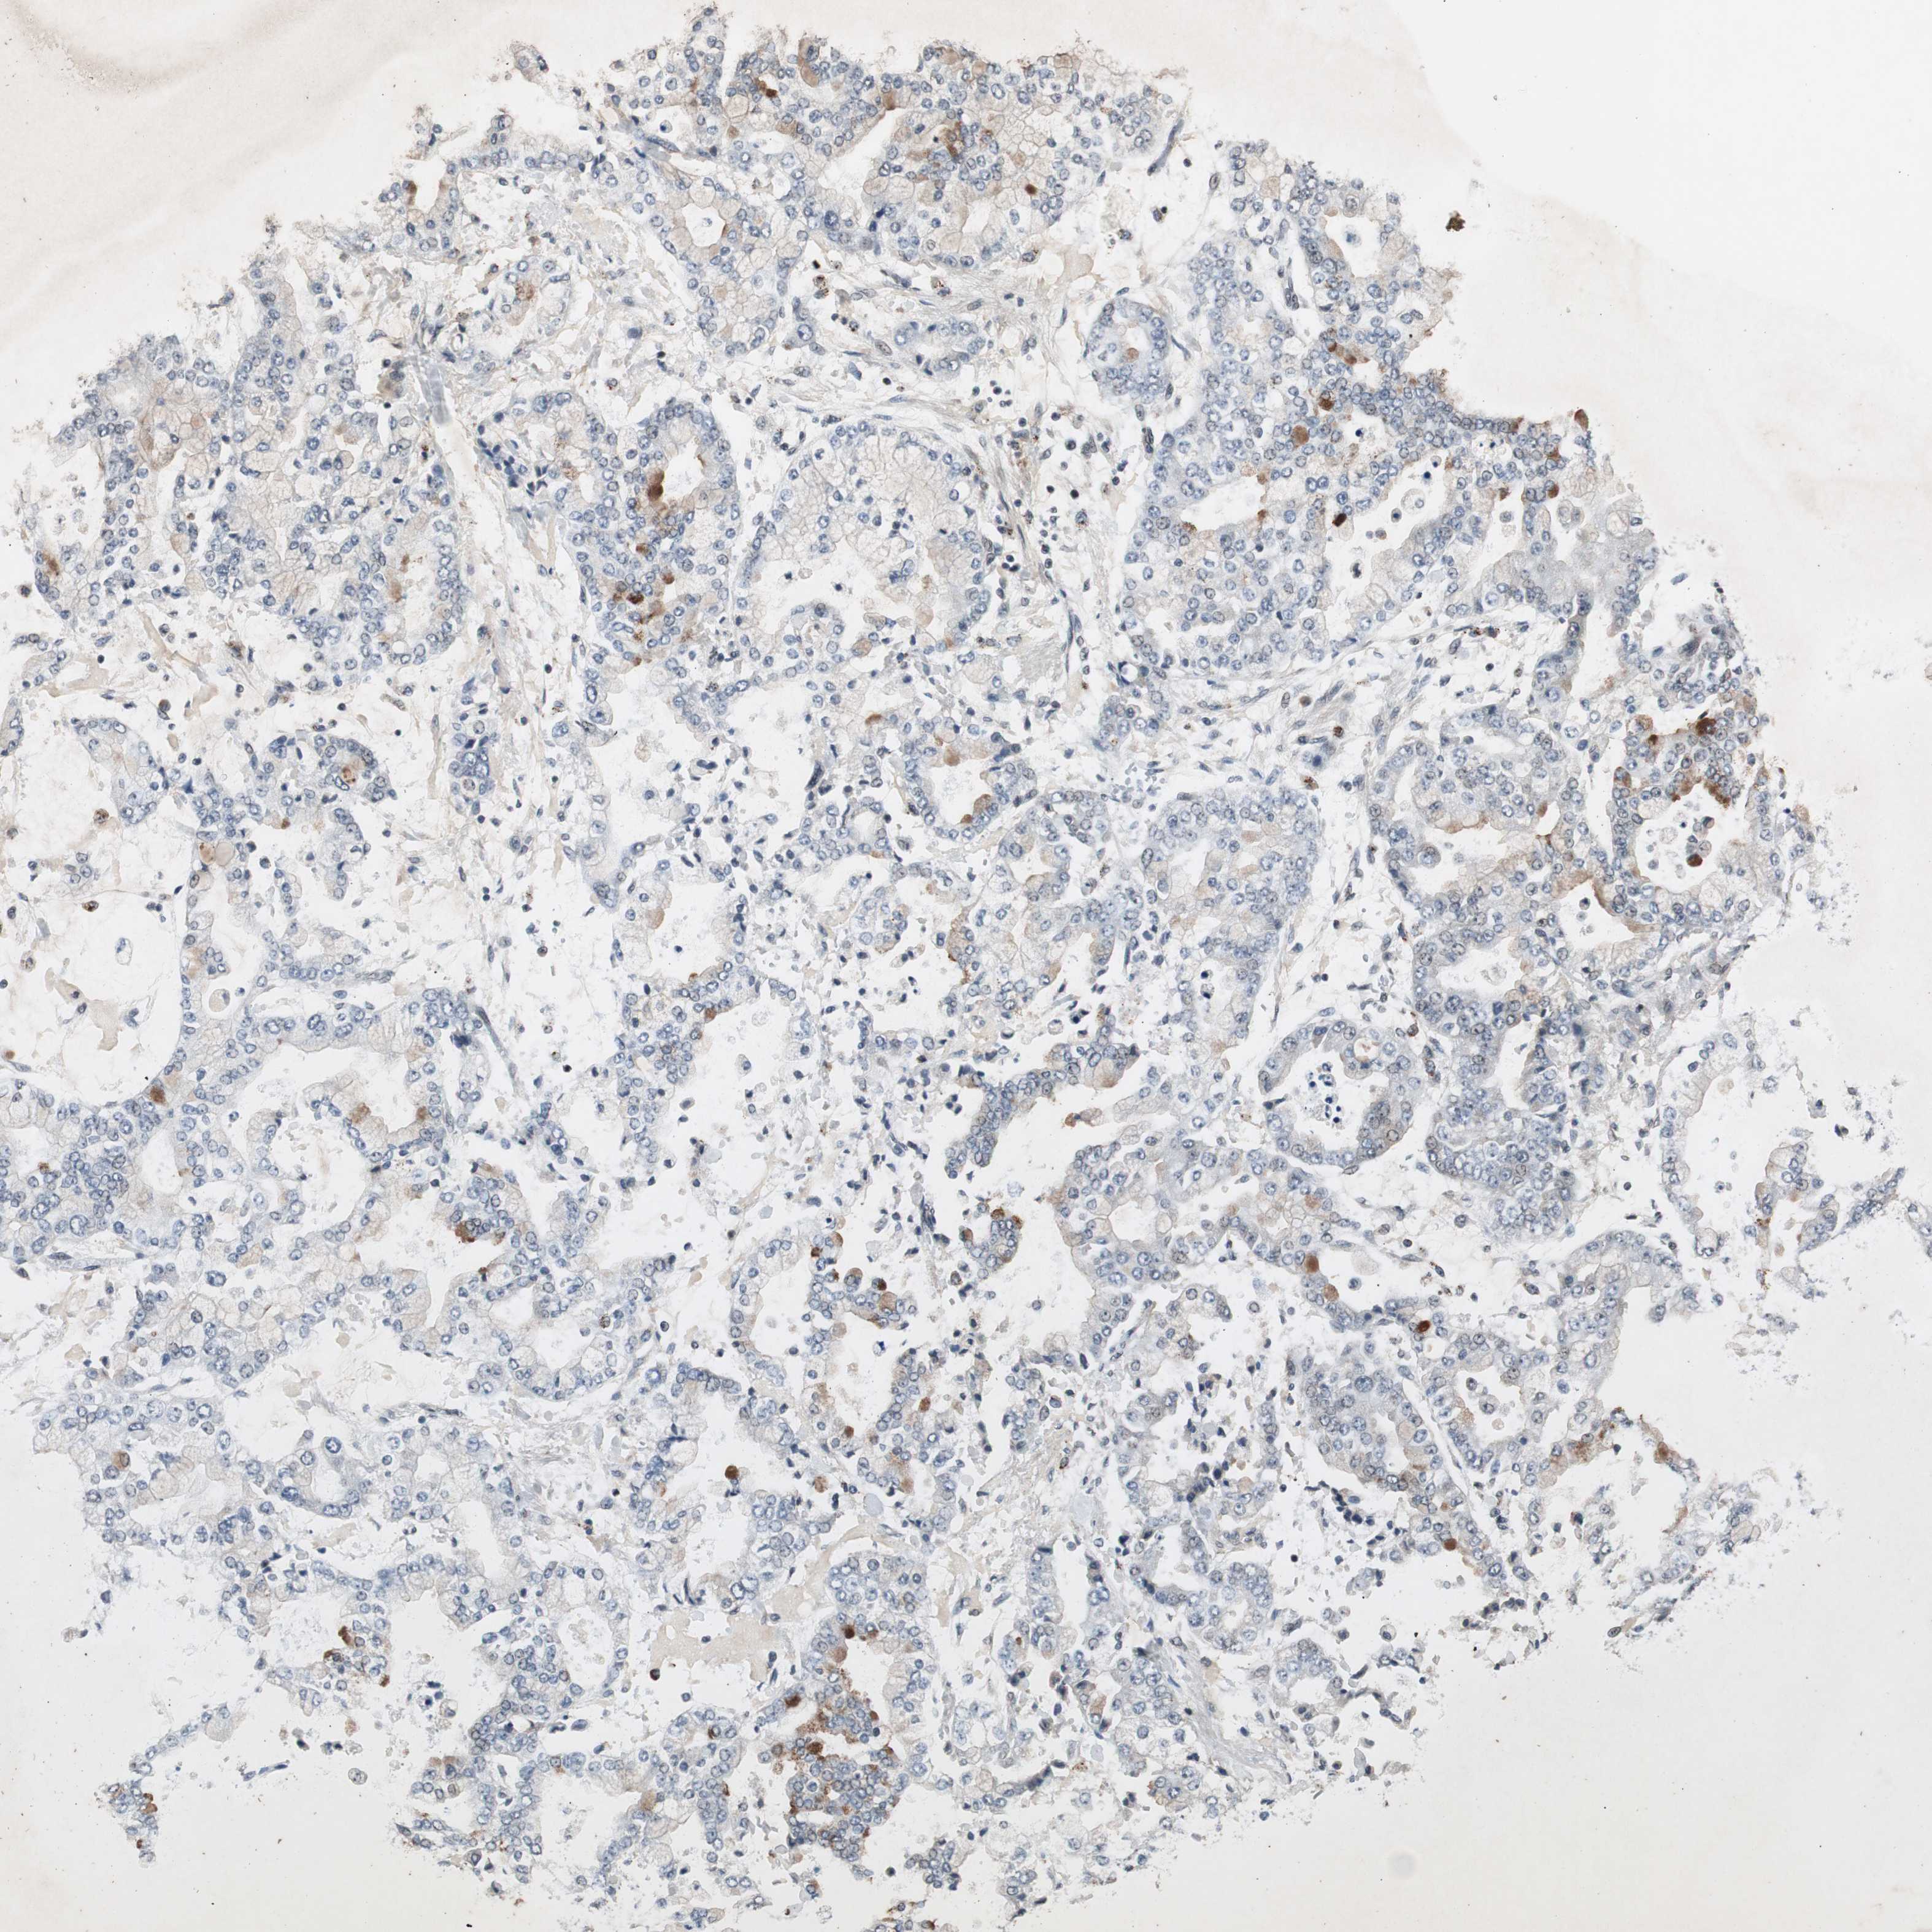

STOMACH CANCER - Protein expressioni

A mouse-over function shows sample information and annotation data. Click on an image to view it in a full screen mode. Samples can be filtered based on level of antibody staining by selecting one or several of the following categories: high, medium, low and not detected. The assay and annotation is described here.

Antibody stainingi

Antibody staining in the annotated cell types in the current human tissue is reported as not detected, low, medium, or high, based on conventional immunohistochemistry profiling in selected tissues. This score is based on the combination of the staining intensity and fraction of stained cells.

Each image is clickable and will lead to virtual microscopy that enables deeper exploration of all samples and also displays staining intensity scores, fraction scores and subcellular localization as well as patient and tissue information for each sample.

Antibody HPA007005

Staining

High

Medium

Low

Not detected

Intensity

Strong

Moderate

Weak

Negative

Quantity

>75%

75%-25%

<25%

None

Location

Nuclear

Cytoplasmic/membranous

Cytoplasmic/membranous,nuclear

Adenocarcinoma, NOS

Adenocarcinoma, High grade